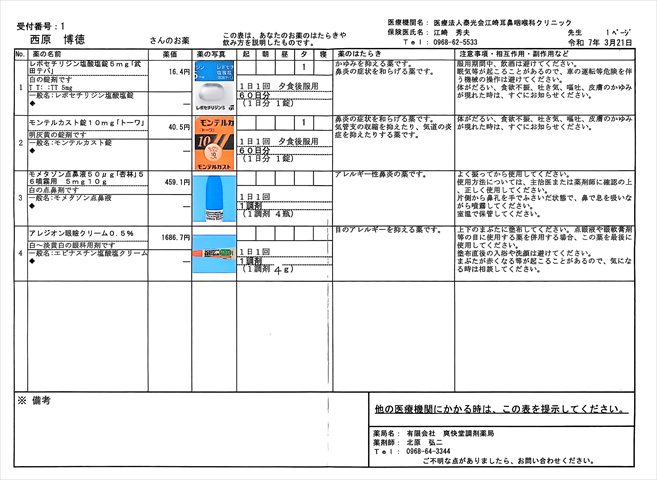

2025.1.31 江崎耳鼻咽喉科

レボセチリジン塩酸塩錠5mg「武田テバ」 モンテルカスト錠10mg「トーワ」